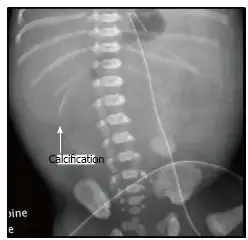

| X-ray of a newborn with meconium pseudocyst resulting from bowel perforation. In this case the cause was atresia of the terminal ileum. There is a fine rim of calcification surrounding the big pseudocyst which shifts the other intestinal structures outwards. | |

Meconium peritonitis refers to rupture of the bowel prior to birth, resulting in fetal stool (meconium) escaping into the surrounding space (peritoneum) leading to inflammation (peritonitis). Despite the bowel rupture, many infants born after meconium peritonitis in utero have normal bowels and have no further issues.

Meconium peritonitis is sometimes diagnosed on prenatal ultrasound[3] where it appears as calcifications[4] within the peritoneum.